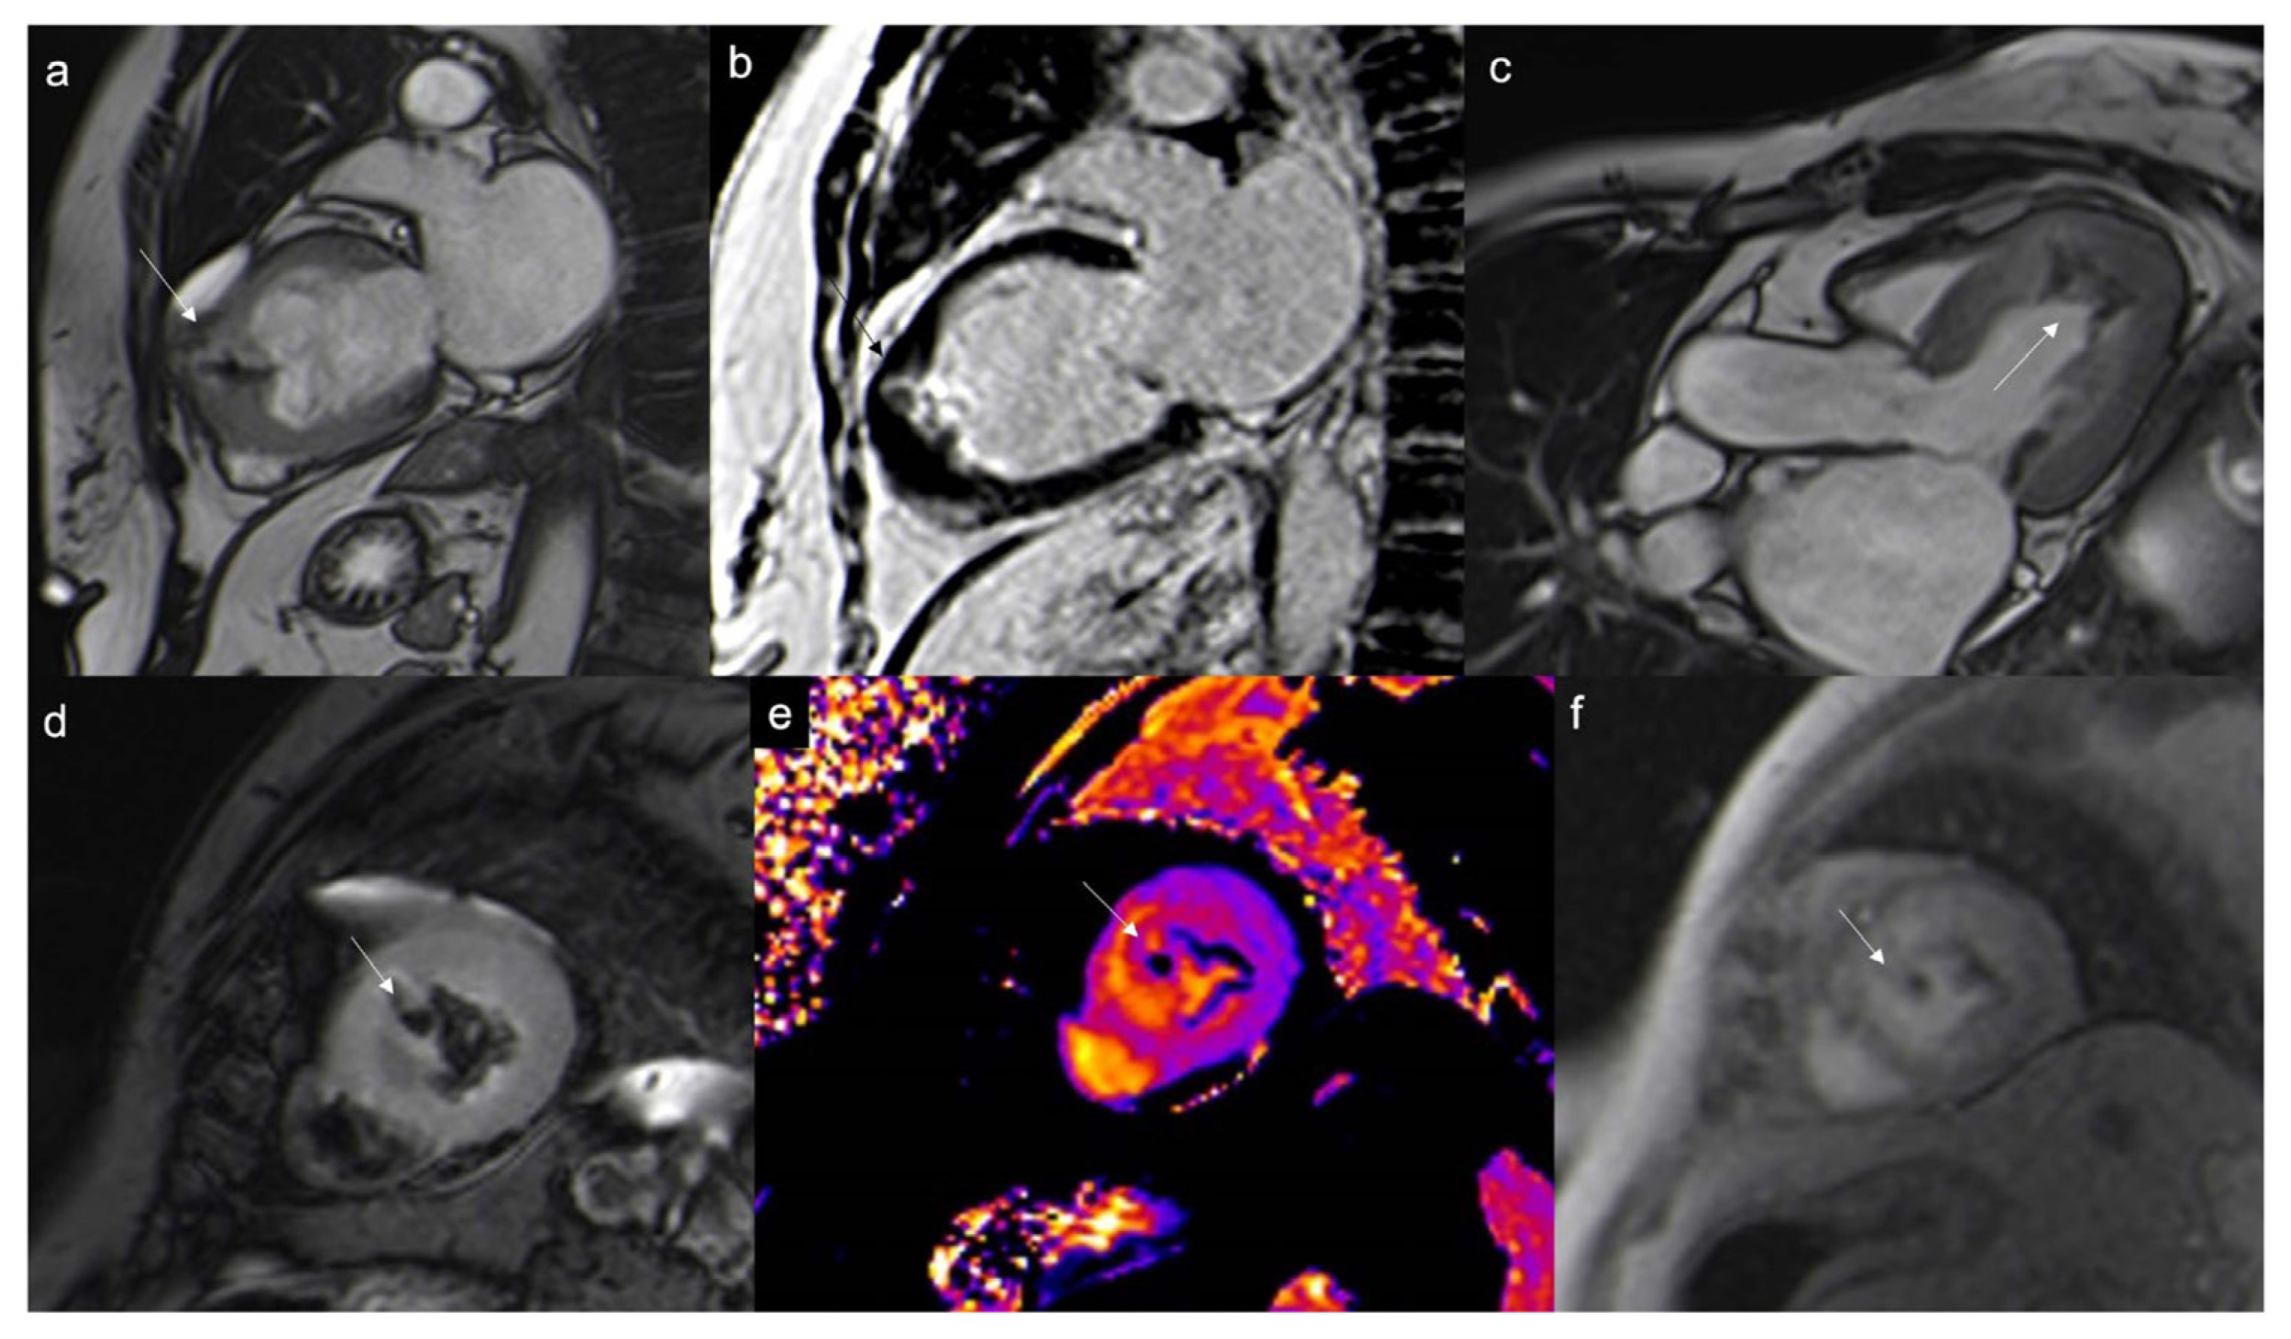

Figure 7.

Typical myxoma (arrow) appears as a well-defined, smooth, oval, or lobular lesion, has an intermediate signal in T1w (a), heterogeneous hyperintensity in T2w and T2w Fat Sat (b,c), linked to the high presence of water in the myxoid stroma. It shows limited enhancement on first-pass perfusion sequences (d) and progressive heterogeneous enhancement on late gadolinium enhancement (LGE) sequences due to its fibrous content (e,f). Some cases may show hyperintensity on T1w images due to hemorrhagic foci. Cine imaging is of particular value in this case as these lesions can be highly mobile and prolapse through the atrioventricular valves during diastole, causing temporary obstruction to blood flow.

Figure 9.

Papillary fibroelastoma of the tricuspid valve (arrow) appears as a highly mobile, spherical pedunculate mass attached to the posterior tricuspid valve leaflet and on T1w images (a) it is homogeneous; no fatty content is found in T2w Fat Sat (b). LGE images demonstrate a hyperintense signal caused by fibroelastic tissue of the mass in 4CH and 2CH of the right ventricle (c,d). Approximately 80% occur concerning either the aortic or mitral valve, while tricuspid and pulmonary involvements are much rarer.

Figure 10.

Neuroendocrine lung tumor with left atrial metastasis due to contiguous spread (a); the atrial mass (arrow) has the same signal as the lung malignant tissue (arrow head) in axial T1w sequences (b), shows heterogeneous enhancement in EGE SA (c), and indicates a slight enhancement in LGE 4CH (d).

Figure 11.

Multiple epi- and intra-myocardial nodules (arrows) along the lateral wall of the left ventricle; subtle hyperintensity on T2w Fat Sat (a) that enhances in LGE (b) in a patient with thymoma.

Figure 12.

Heterogeneous right atrial mass (arrow) iso-hypointense in T1w and slightly hyperintense in T2w Fat Sat (a,b), with inhomogeneous enhancement in LGE axial acquisition (c), turned out to be an angiosarcoma. After multiple cycles of chemotherapy and radiotherapy, there was no perceptible enhancement in LGE SAX acquisition (d).

Figure 13.

Rhabdomyosarcoma (arrow) is hyperintense on T2-weighted images (a) and it shows contrast enhancement with regions of hypointensity due to central necrosis (b).